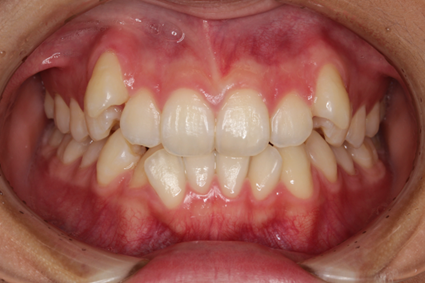

歯がデコボコに並んだ歯並びのことを「叢生(そうせい)」と言います。「乱ぐい歯」という名前でも知られています。叢生の歯並びの中で、よく知られているのが、上顎の犬歯が前方に突出している「八重歯」です。八重歯は可愛らしいイメージに捉えられることもありますが、歯並びとしては良くない、デコボコ歯並びの一種です。

叢生の原因は、顎の骨が小さく、歯が並ぶための十分なスペースが確保できないことが挙げられます。

叢生による問題は、見た目だけではありません。次のような様々な「リスク」があります。